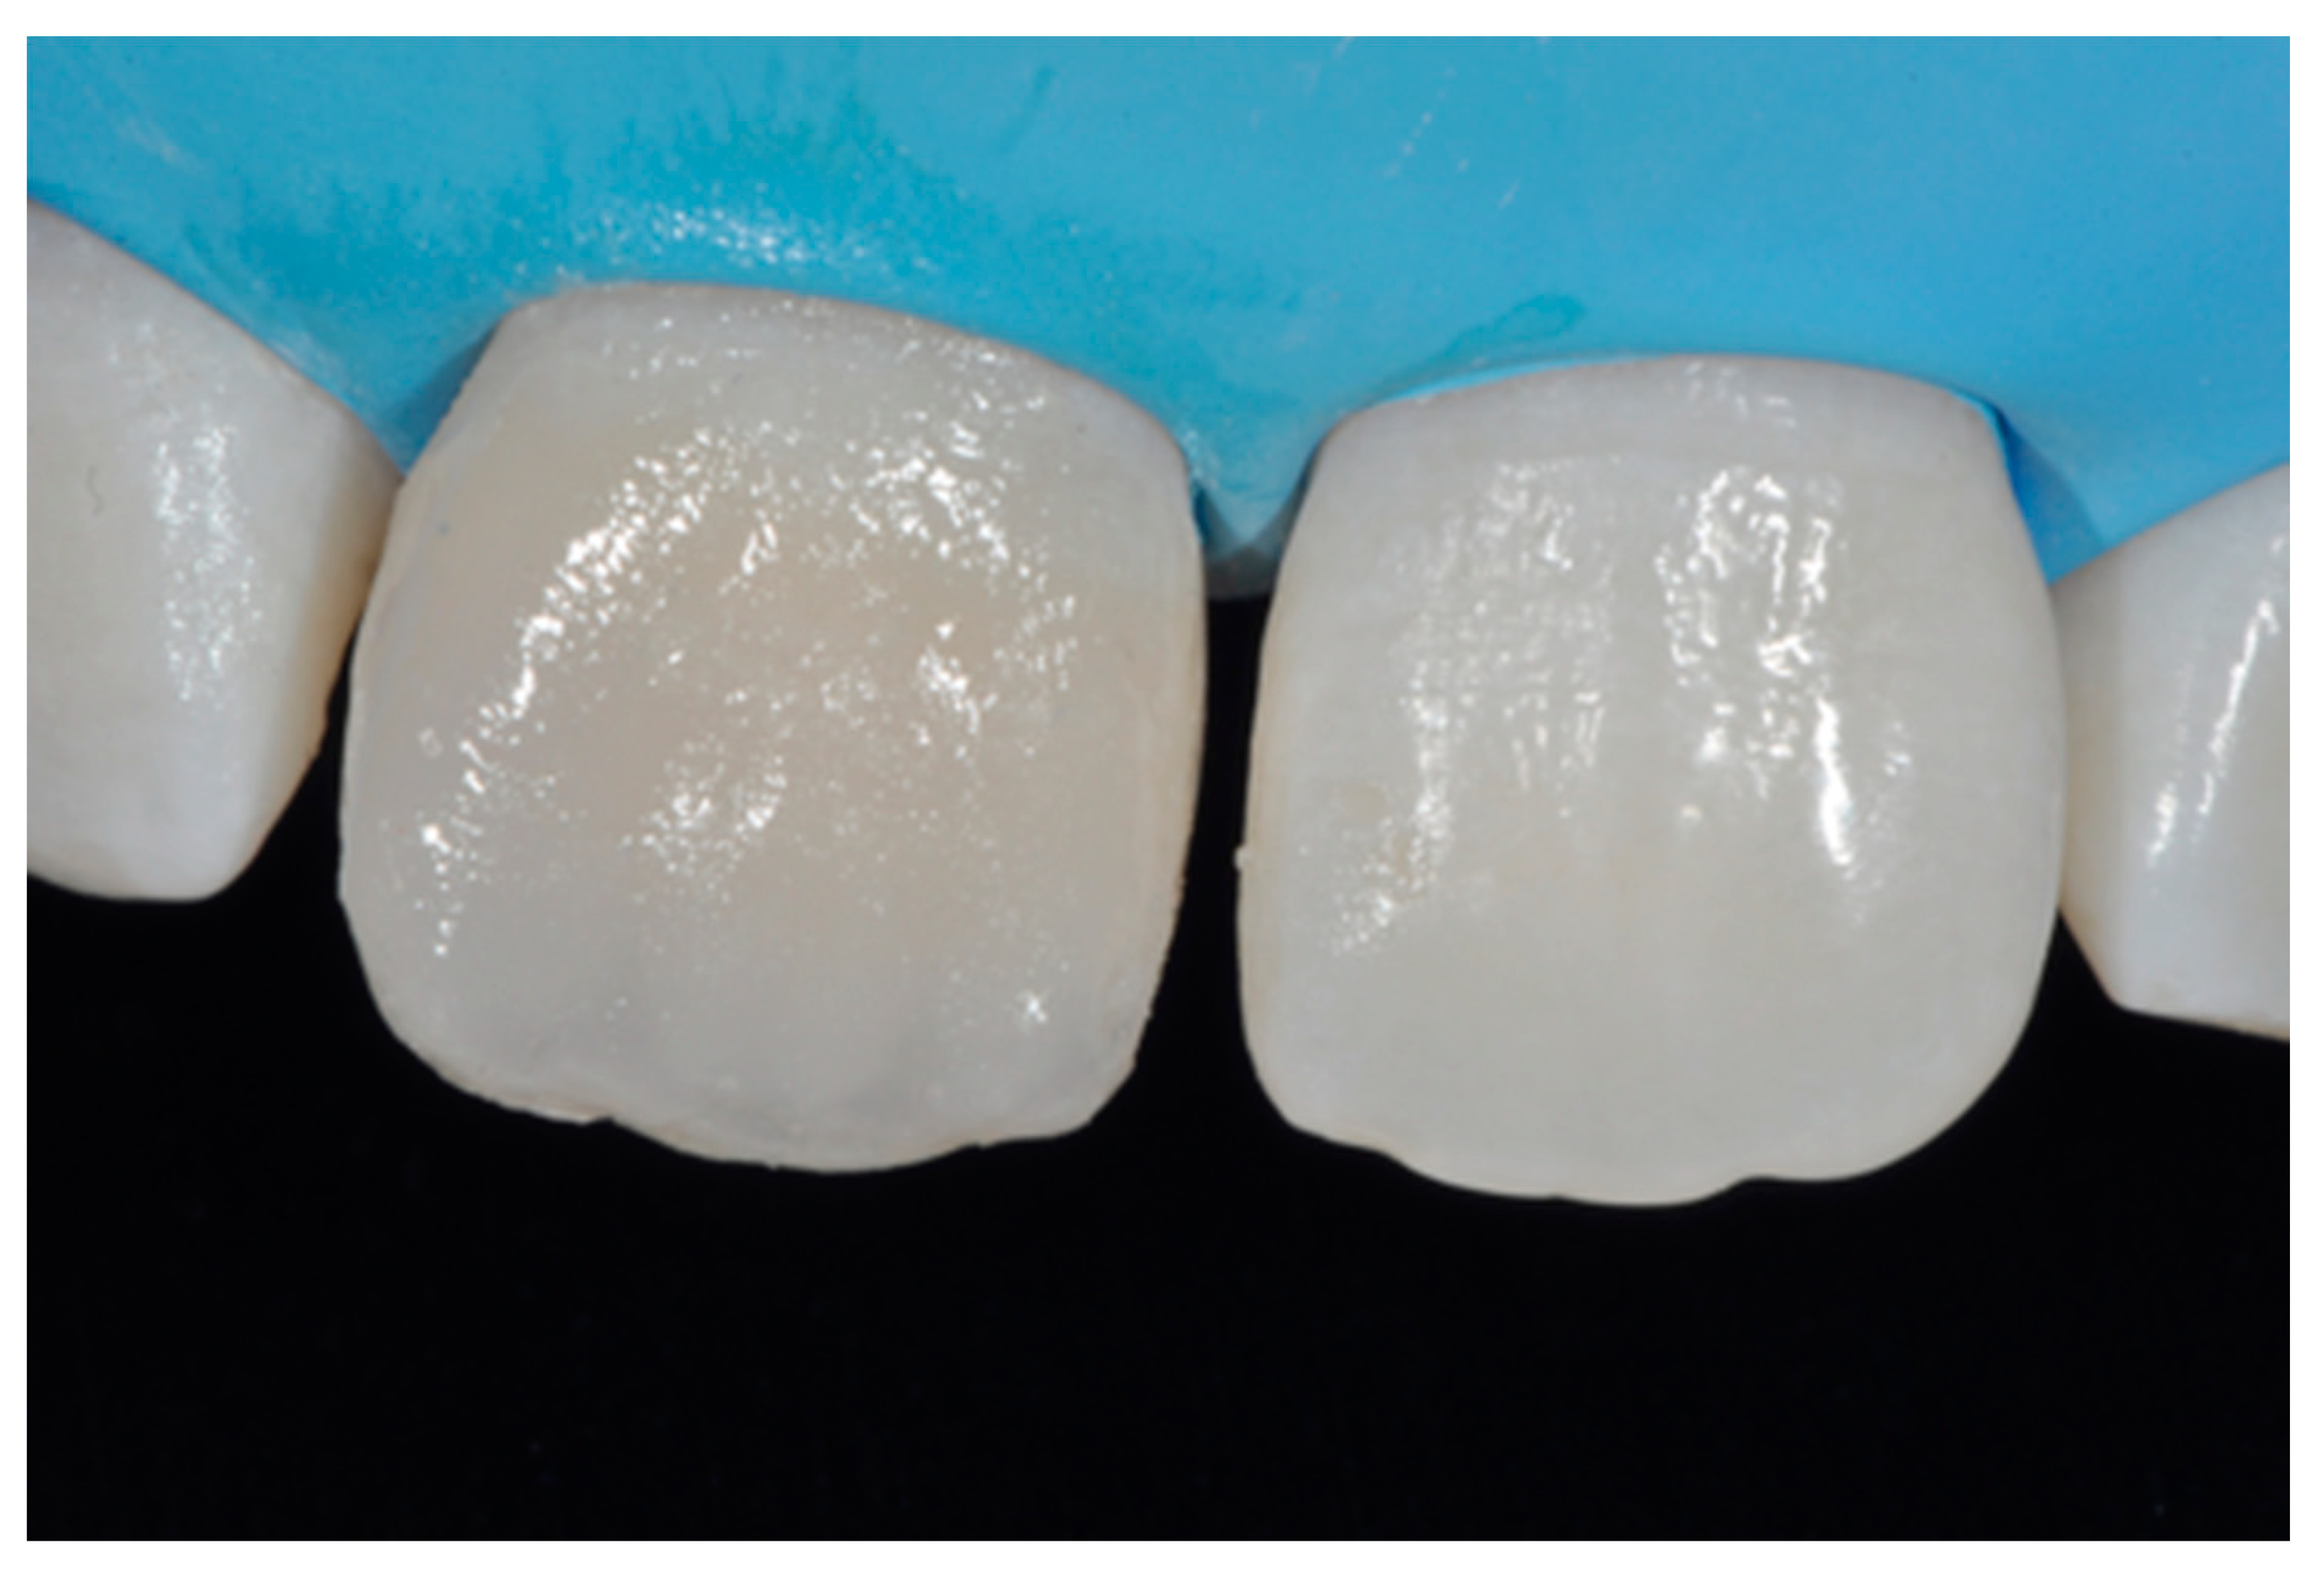

2.1.3. Completion of the Layering Procedure, Finishing and Polishing

A single shade of dentin (Clearfil Majesty ES-2, A1D, Kuraray Noritake Dental, Tokyo, Japan) was then applied placing separate increments (Figure 10 and Figure 11) to build the dentinal body, leaving space for incisal translucencies. The translucent shade (Clearfil Majesty ES-2, A1E, Kuraray Noritake Dental, Tokyo, Japan) was then applied to complete the restoration (Figure 12).

Figure 11.

Dentinal body completed. Reprinted from Restauri diretti nei settori anteriori, G. Paolone, S. Scolavino, © 2021, with permission from Quintessence Publishing Italy.